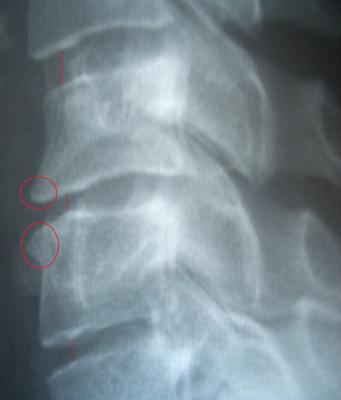

Auf dem Bild habe ich mit Strichen die Bandscheibendicken angedeutet. Mann kann sehen, dass die beiden unteren deutlich dünner sind als die obere. In den Kreisen sind die Verformungen der Wirbelkörper zu sehen, die als Folge des Bandscheibenschadens über die Jahre entstanden sind.

Hier sind die Bilder auch nochmal in groß:

Halswirbelsäule:

Bild

Bandscheiben: